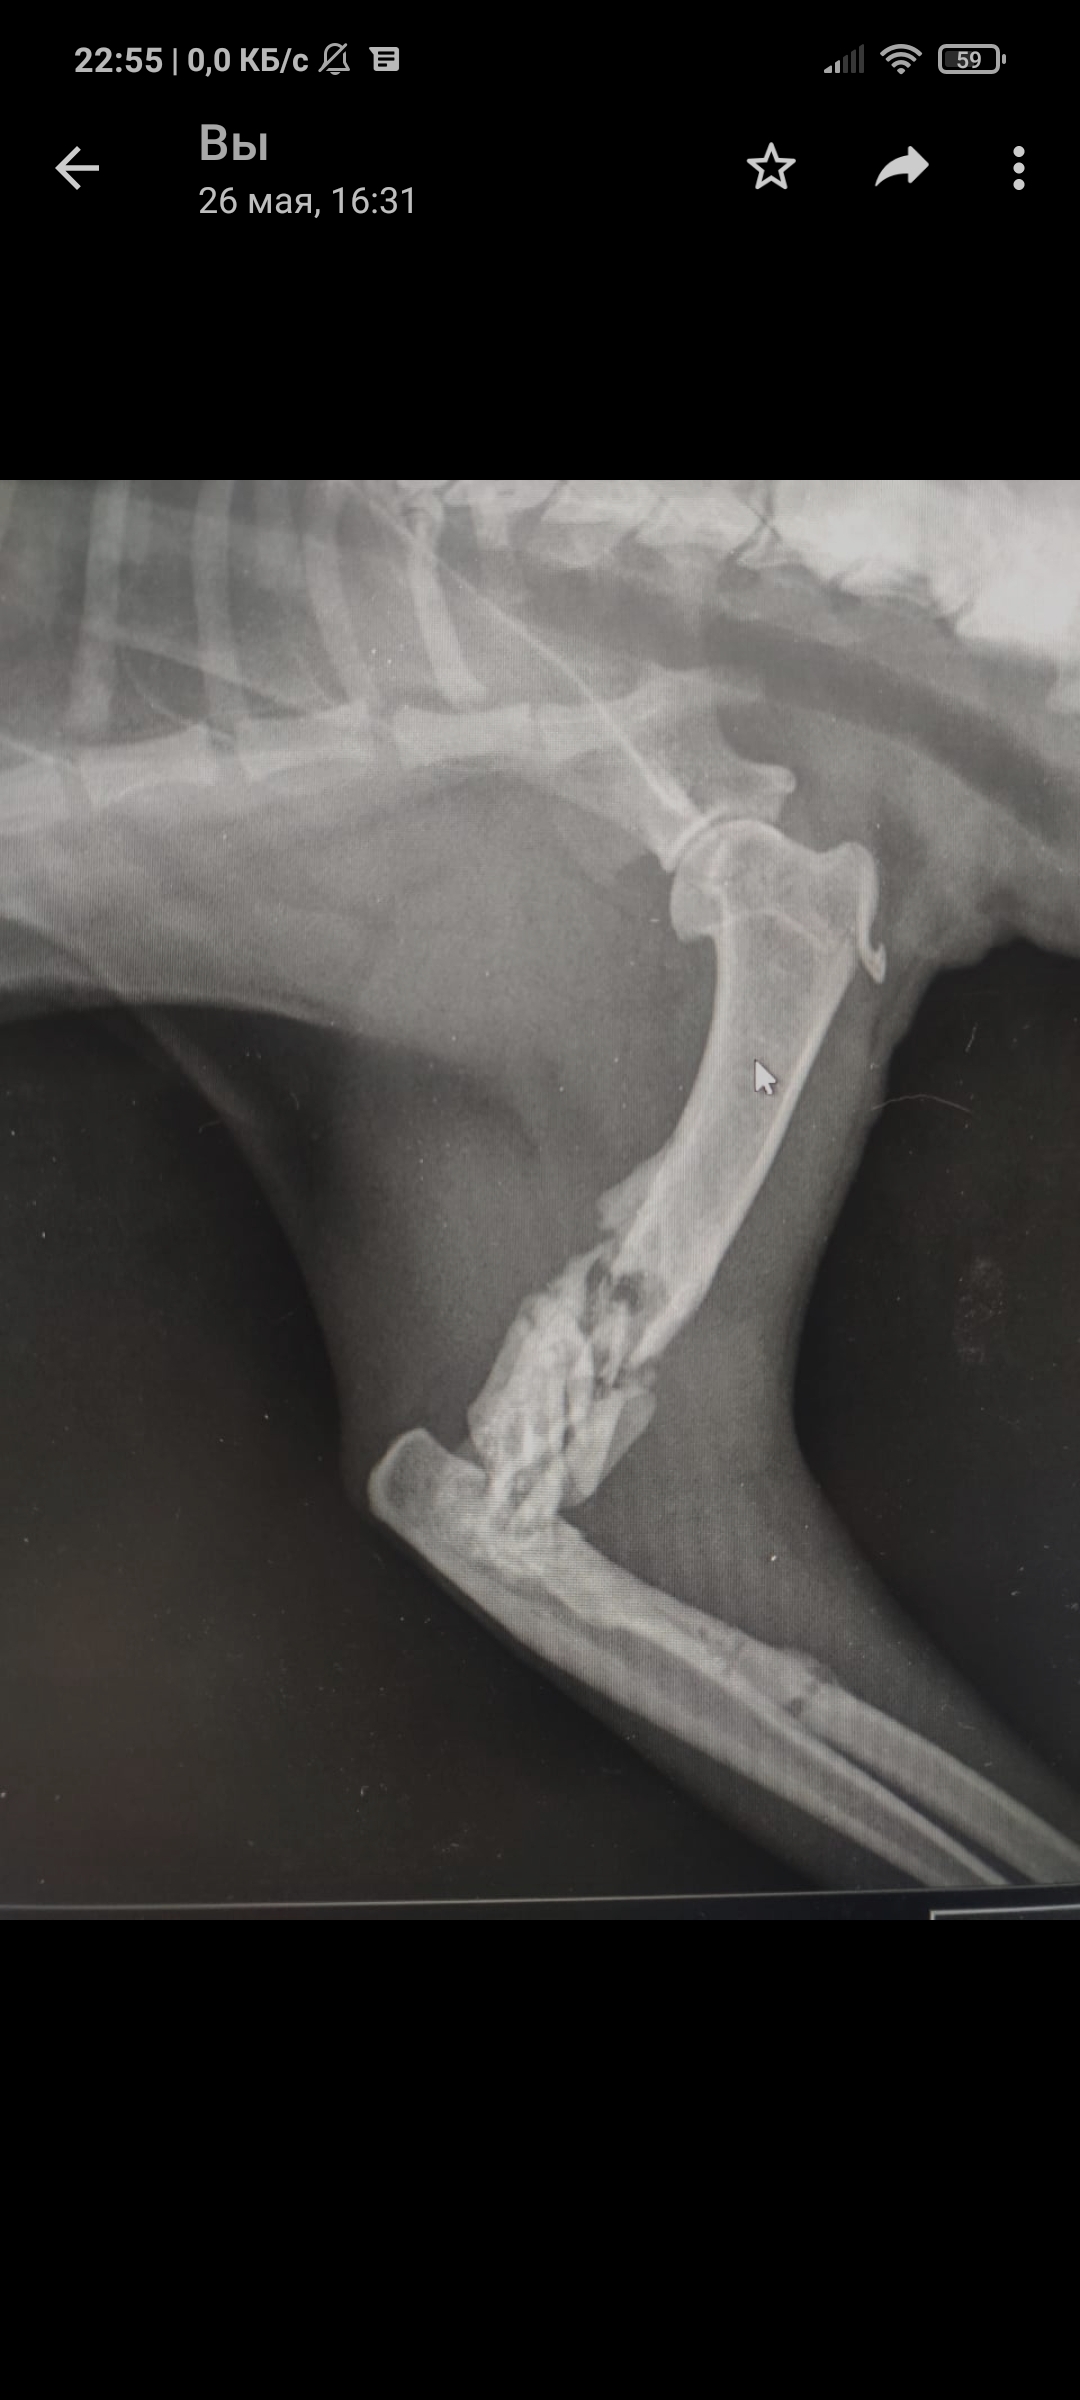

Так уж получилось что я ветеринарный врач, работаю в интенсивной терапии - принимаю и лечу самых тяжелых животных. На днях ближе к ночи прибегает женщина с котом, который шлёпнулся перед ней на улице. При осмотре выясняется что кот в шоке - лежит на боку, без давления, температуры, у него сломаны передние лапы, лицо, пневмоторакс и немного жидкости в брюшной полости (вероятно кровь). Женщина оставляет двадцатку на первые сутки и идет искать хозяина, кот помещается в стационар для стабилизации состояния. Всю ночь я ебусь с этим котом, вывожу его из шока, спускаю ему пневмоторакс, грею, обезболы льются рекой, к утру кот похож на кота, а не на покойника - начал садиться, ползать, полизал еду.